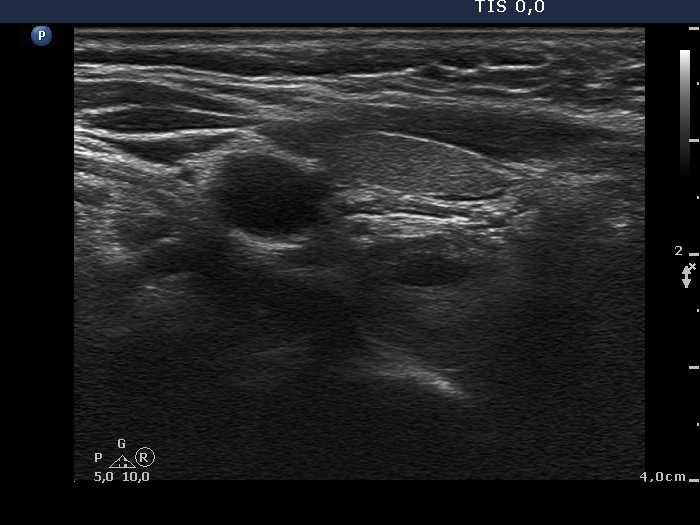

Clinical data: A 63-year-old woman was referred for exact localization of a parathyroid before surgery. The patient had diffuse complaints, including fatigue, depression, weight loss. On routine laboratory blood test, an elevated serum calcium level, thereafter an elevated parathormone level (154 pg/mL) were detected. MIBI scintigraphy disclosed parathyroid adenoma corresponding to the right lower parathyroid.

Ultrasonography. The thyroid was minimally hypoechoic and had several insignificant hypoechoic lesions. There was a solid-cystic mass dorsal to the lower pole of the right lobe.

Aspiration cytology of the lesion was performed. There were only scattered, non-atypical epithelial cells on the smear which was gained form a small amount of serous tissue.